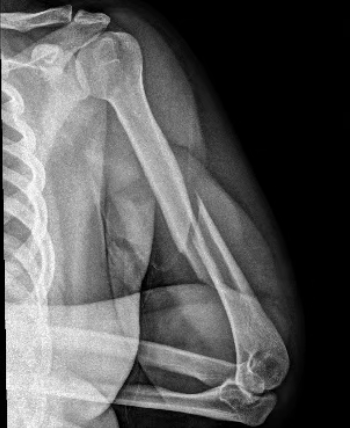

朋友嚇壞了,趕緊將他送至泉州市正骨醫(yī)院。上肢科葉春曉副主任醫(yī)師接診后,通過詳細(xì)查體并結(jié)合X光檢查,迅速確診為肱骨干螺旋形骨折——一種典型的因扭轉(zhuǎn)暴力導(dǎo)致的骨折類型。

X光片顯示螺旋形肱骨干骨折